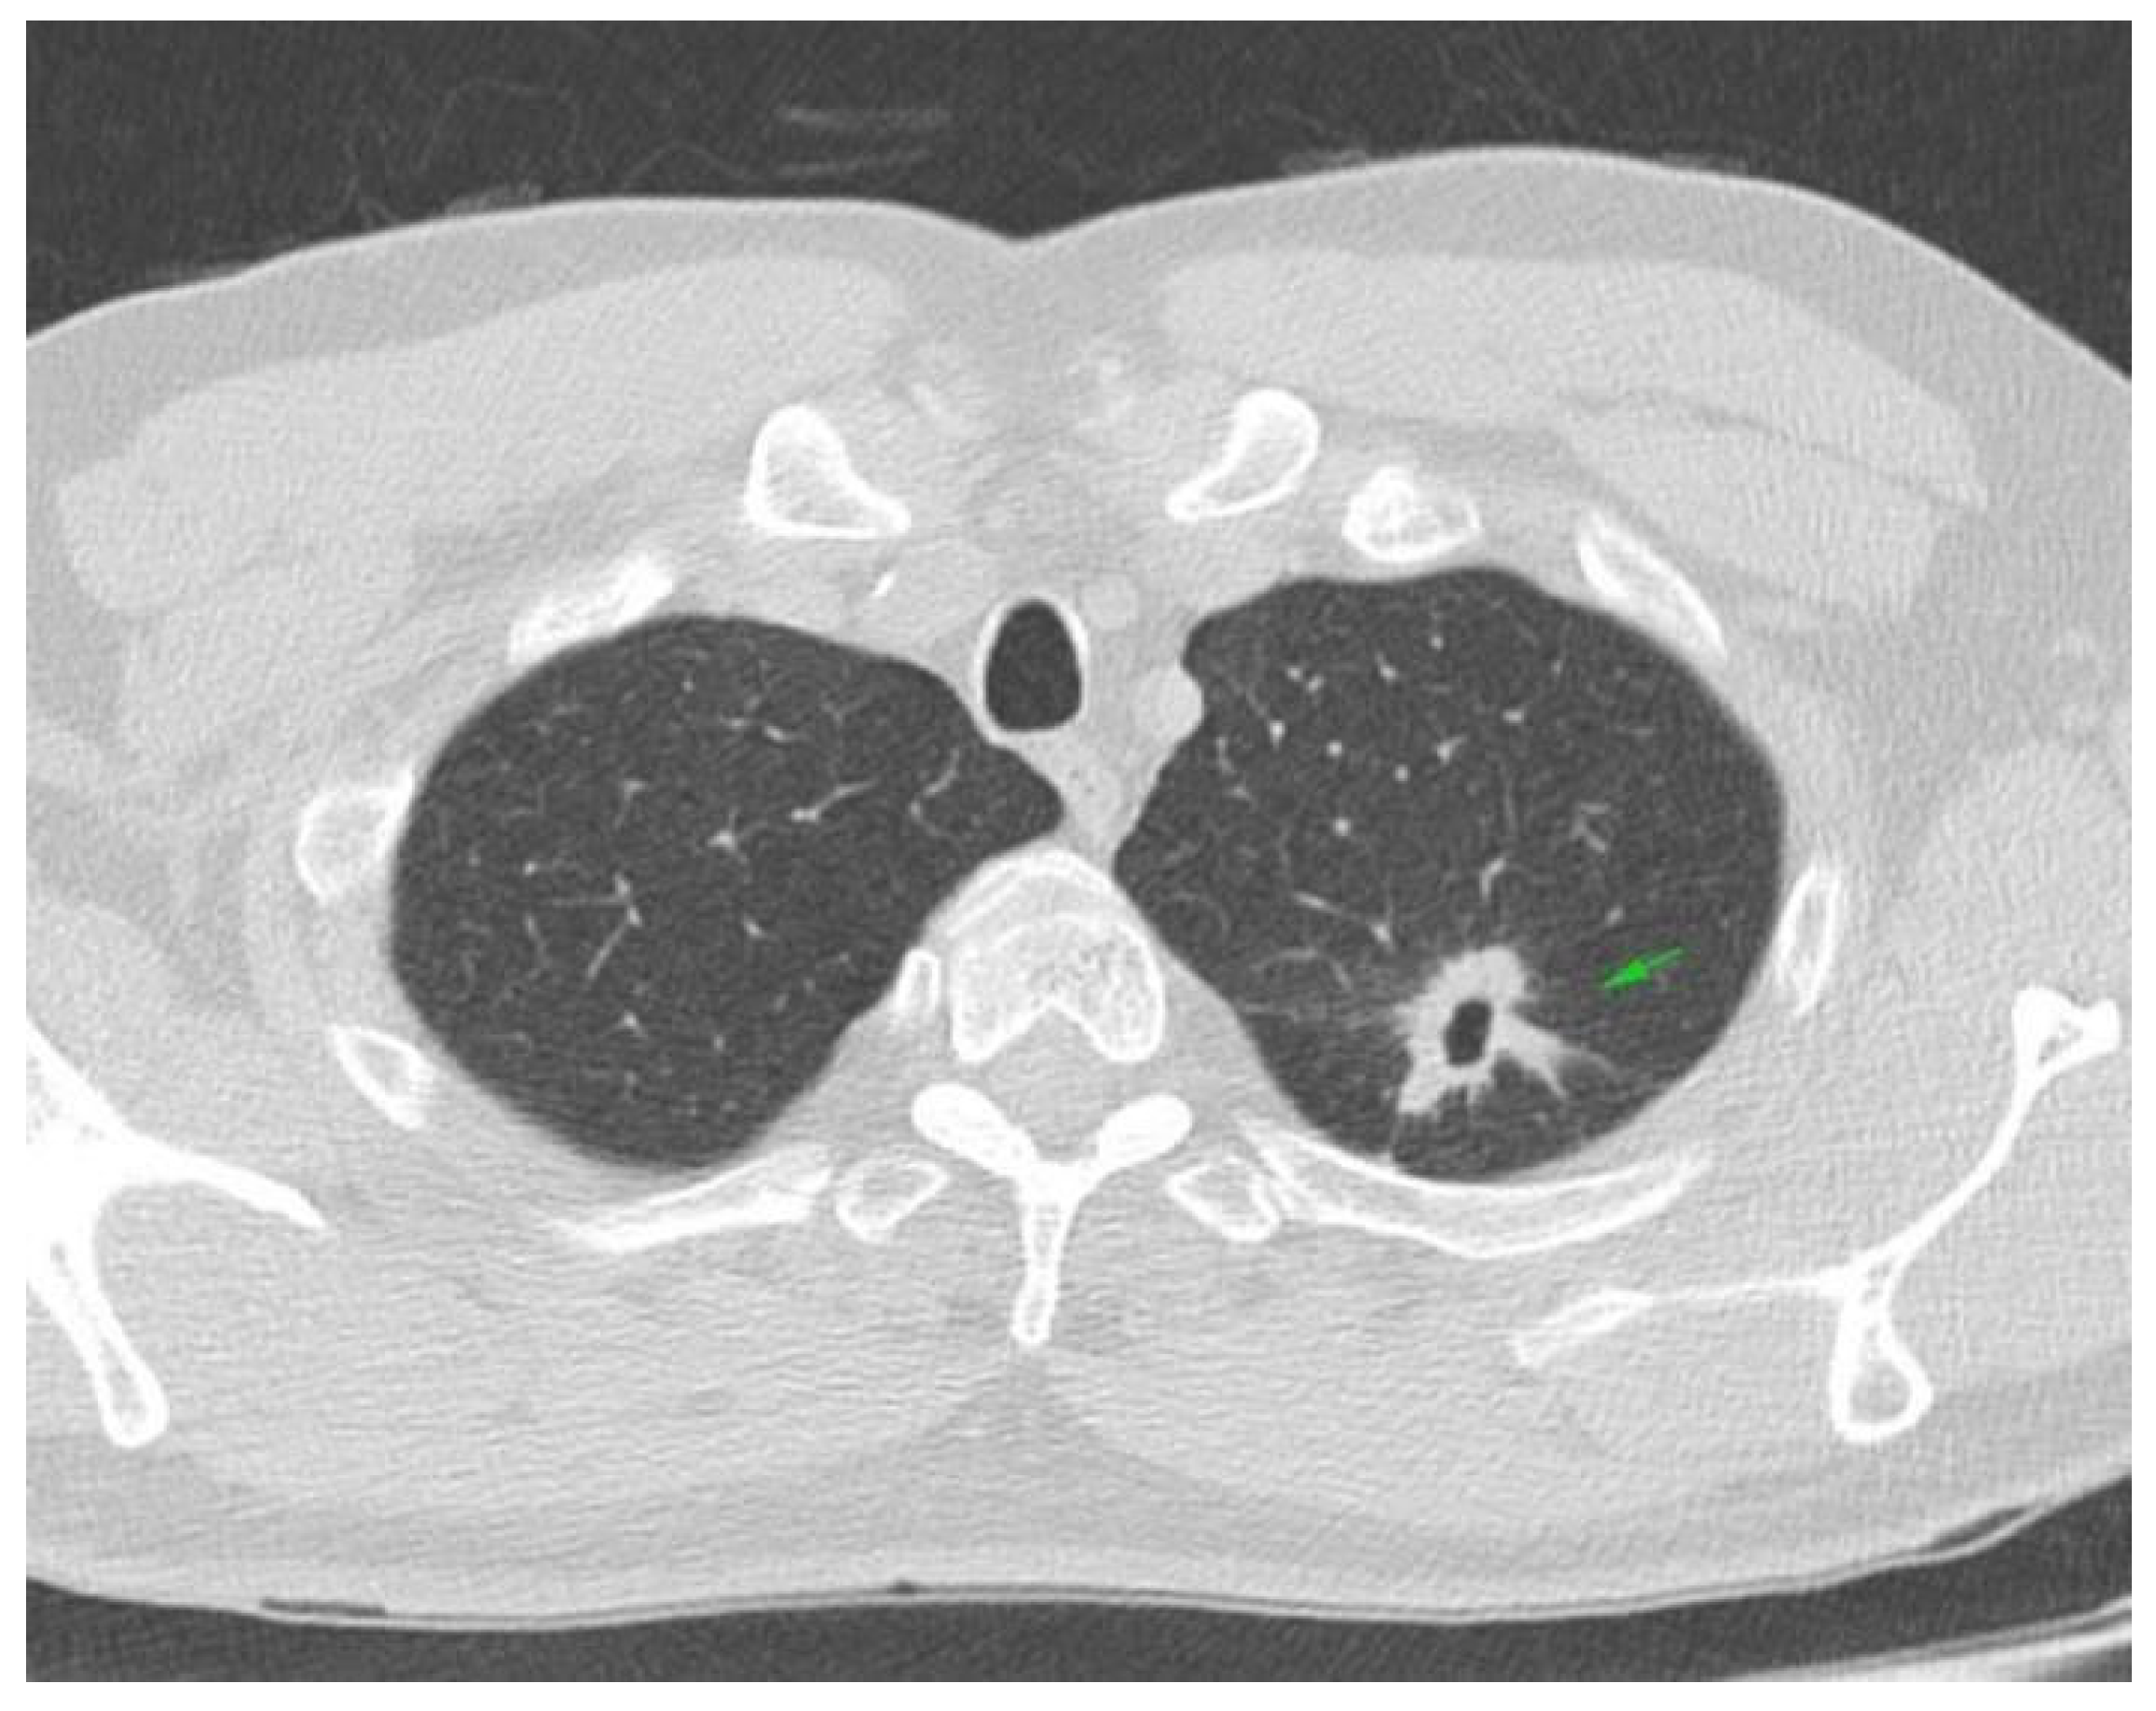

2. Case Presentation